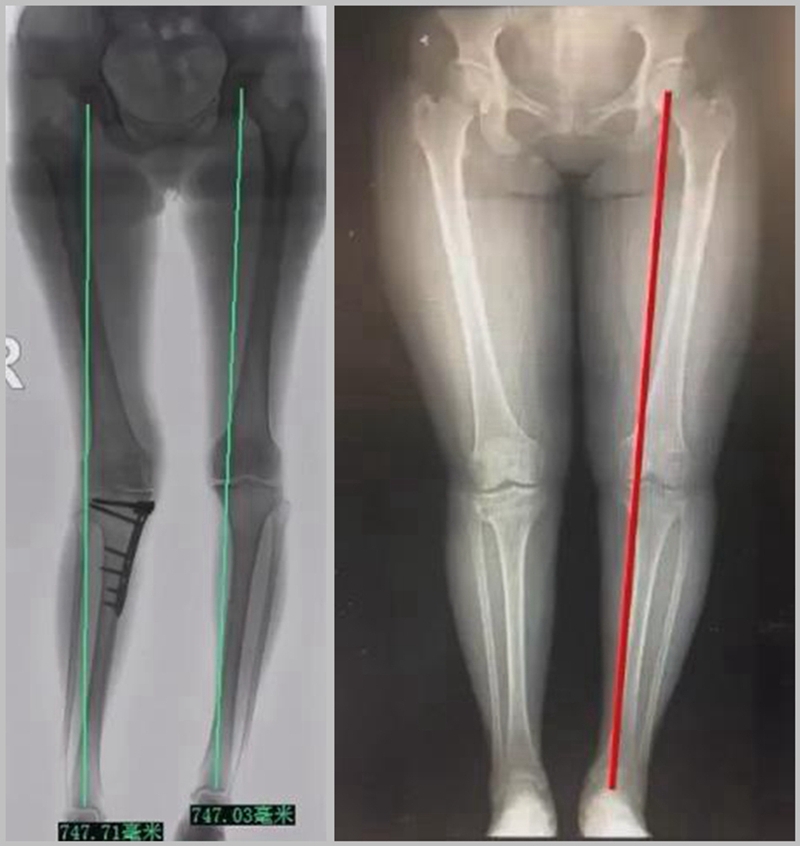

二、矫正不良

截骨实际上是通过力线的重新分布来调整好关节的压力,但是经常会出现矫正过度或者矫正不良的问题。

1、综合判断力线的方法

现在对于力线的判断大致通过以下几方面:①大体形态;②透视确定力线,连接股骨头中心、踝关节中心,看力线杆和膝关节中心的位置关系;③MPTA(胫骨平台关节线和胫骨侧机械轴夹角);④PSI。

1、原因及预防

(1)肢体外旋

一般来说在麻醉状态下肢体会处于外旋位,此时去测定力线的话往往需要将肢体放在旋转中立位,但是在内旋肢体的过程中会出现内翻应力,那么这种情况下判断力线会带来误差,所以通常建议大家要把手术床做一点旋转,让患肢处于自然的旋转中立位,这样再去判断力线就比较准确。

(2)MCL浅层未彻底松解

对于MCL,大多数忽视的是后侧束,如果不能把后侧束彻底松解,那么在撑开过程中往往会感觉撑不开,此时如果过度去撑开的话,会导致在关节内侧出现很大的压力,所以这时对力线会产生一定的误导。

(3)力线验证未模仿负重应力

现在所谓的目标力线应该是模仿负重时的力线。做截骨时,通常会将力线轻度外移,如果没有考虑关节内畸形、韧带松弛或是软骨磨损,那么在负重时,在内侧副韧带撑开过程中,会出现力线偏移。所以要注意,手术中间在调整目标力线时,要以应力状态下为标准。

(4)拉力螺钉加压过度

拉力螺钉的过度使用可能会引起矫形位置的角度丢失。当拉力过度时,会将力线由内侧向外侧轻度拉回,使力线丢失一部分,所以切忌过度使用。